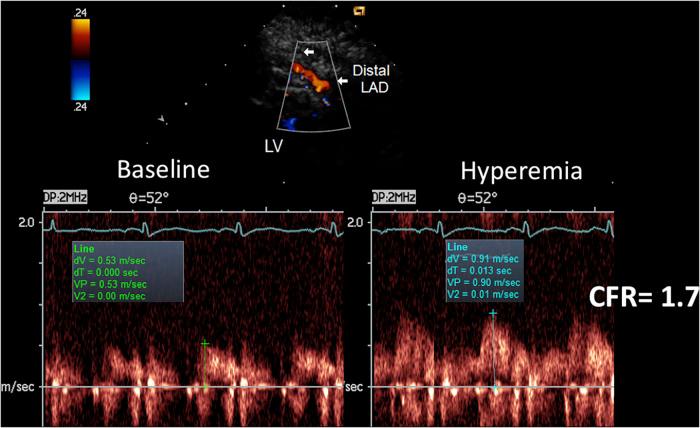

Accelerated stenotic flow (AsF) in the entire left anterior descending coronary artery (LAD), assessed by transthoracic enhanced color Doppler (E-Doppler TTE), can reveal coronary stenosis (CS) and its severity, enabling a distinction between the microcirculatory and epicardial causes of coronary flow reserve (CFR) impairment.

Eighty-four consecutive patients with a CFR <2.0 (1.5 ± 0.4), as assessed by E-Doppler TTE, scheduled for coronary angiography (CA) and eventually intracoronary ultrasounds (IVUS), were studied. CFR was calculated by the ratio of peak diastolic flow velocities: during i.v. adenosine (140 mcg/Kg/m) over resting; AsF was calculated as the percentage increase of localized maximal velocity in relation to a reference velocity.

经胸增强彩色多普勒(E-Doppler TTE)评估的整个左前降支冠状动脉(LAD)中的加速狭窄血流(AsF),可揭示冠状动脉狭窄(CS)及其严重程度,从而能够区分冠状动脉血流储备(CFR)受损的微循环和心外膜原因。

对84例连续患者进行了研究,这些患者经E-Doppler TTE评估CFR<2.0(1.5±0.4),计划进行冠状动脉造影(CA)并最终进行血管内超声(IVUS)检查。CFR通过舒张末期峰值流速之比计算:静脉注射腺苷(140μg/Kg/m)时的流速与静息时的流速之比;AsF计算为局部最大速度相对于参考速度的增加百分比。